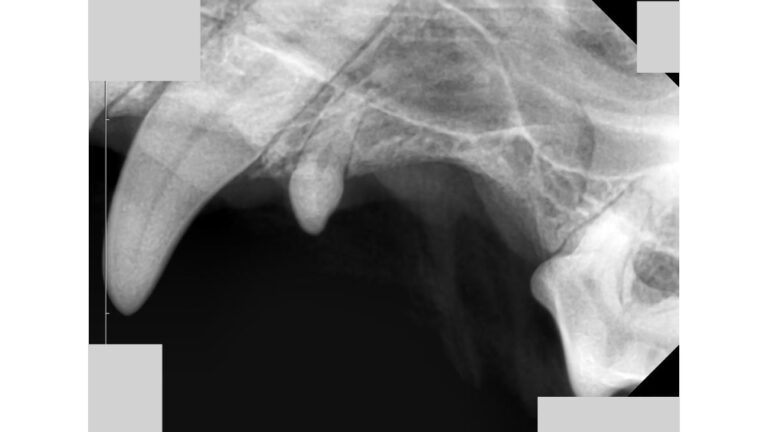

【歯科】小型犬に多い、欠損歯とは

投稿日

2023年11月15日